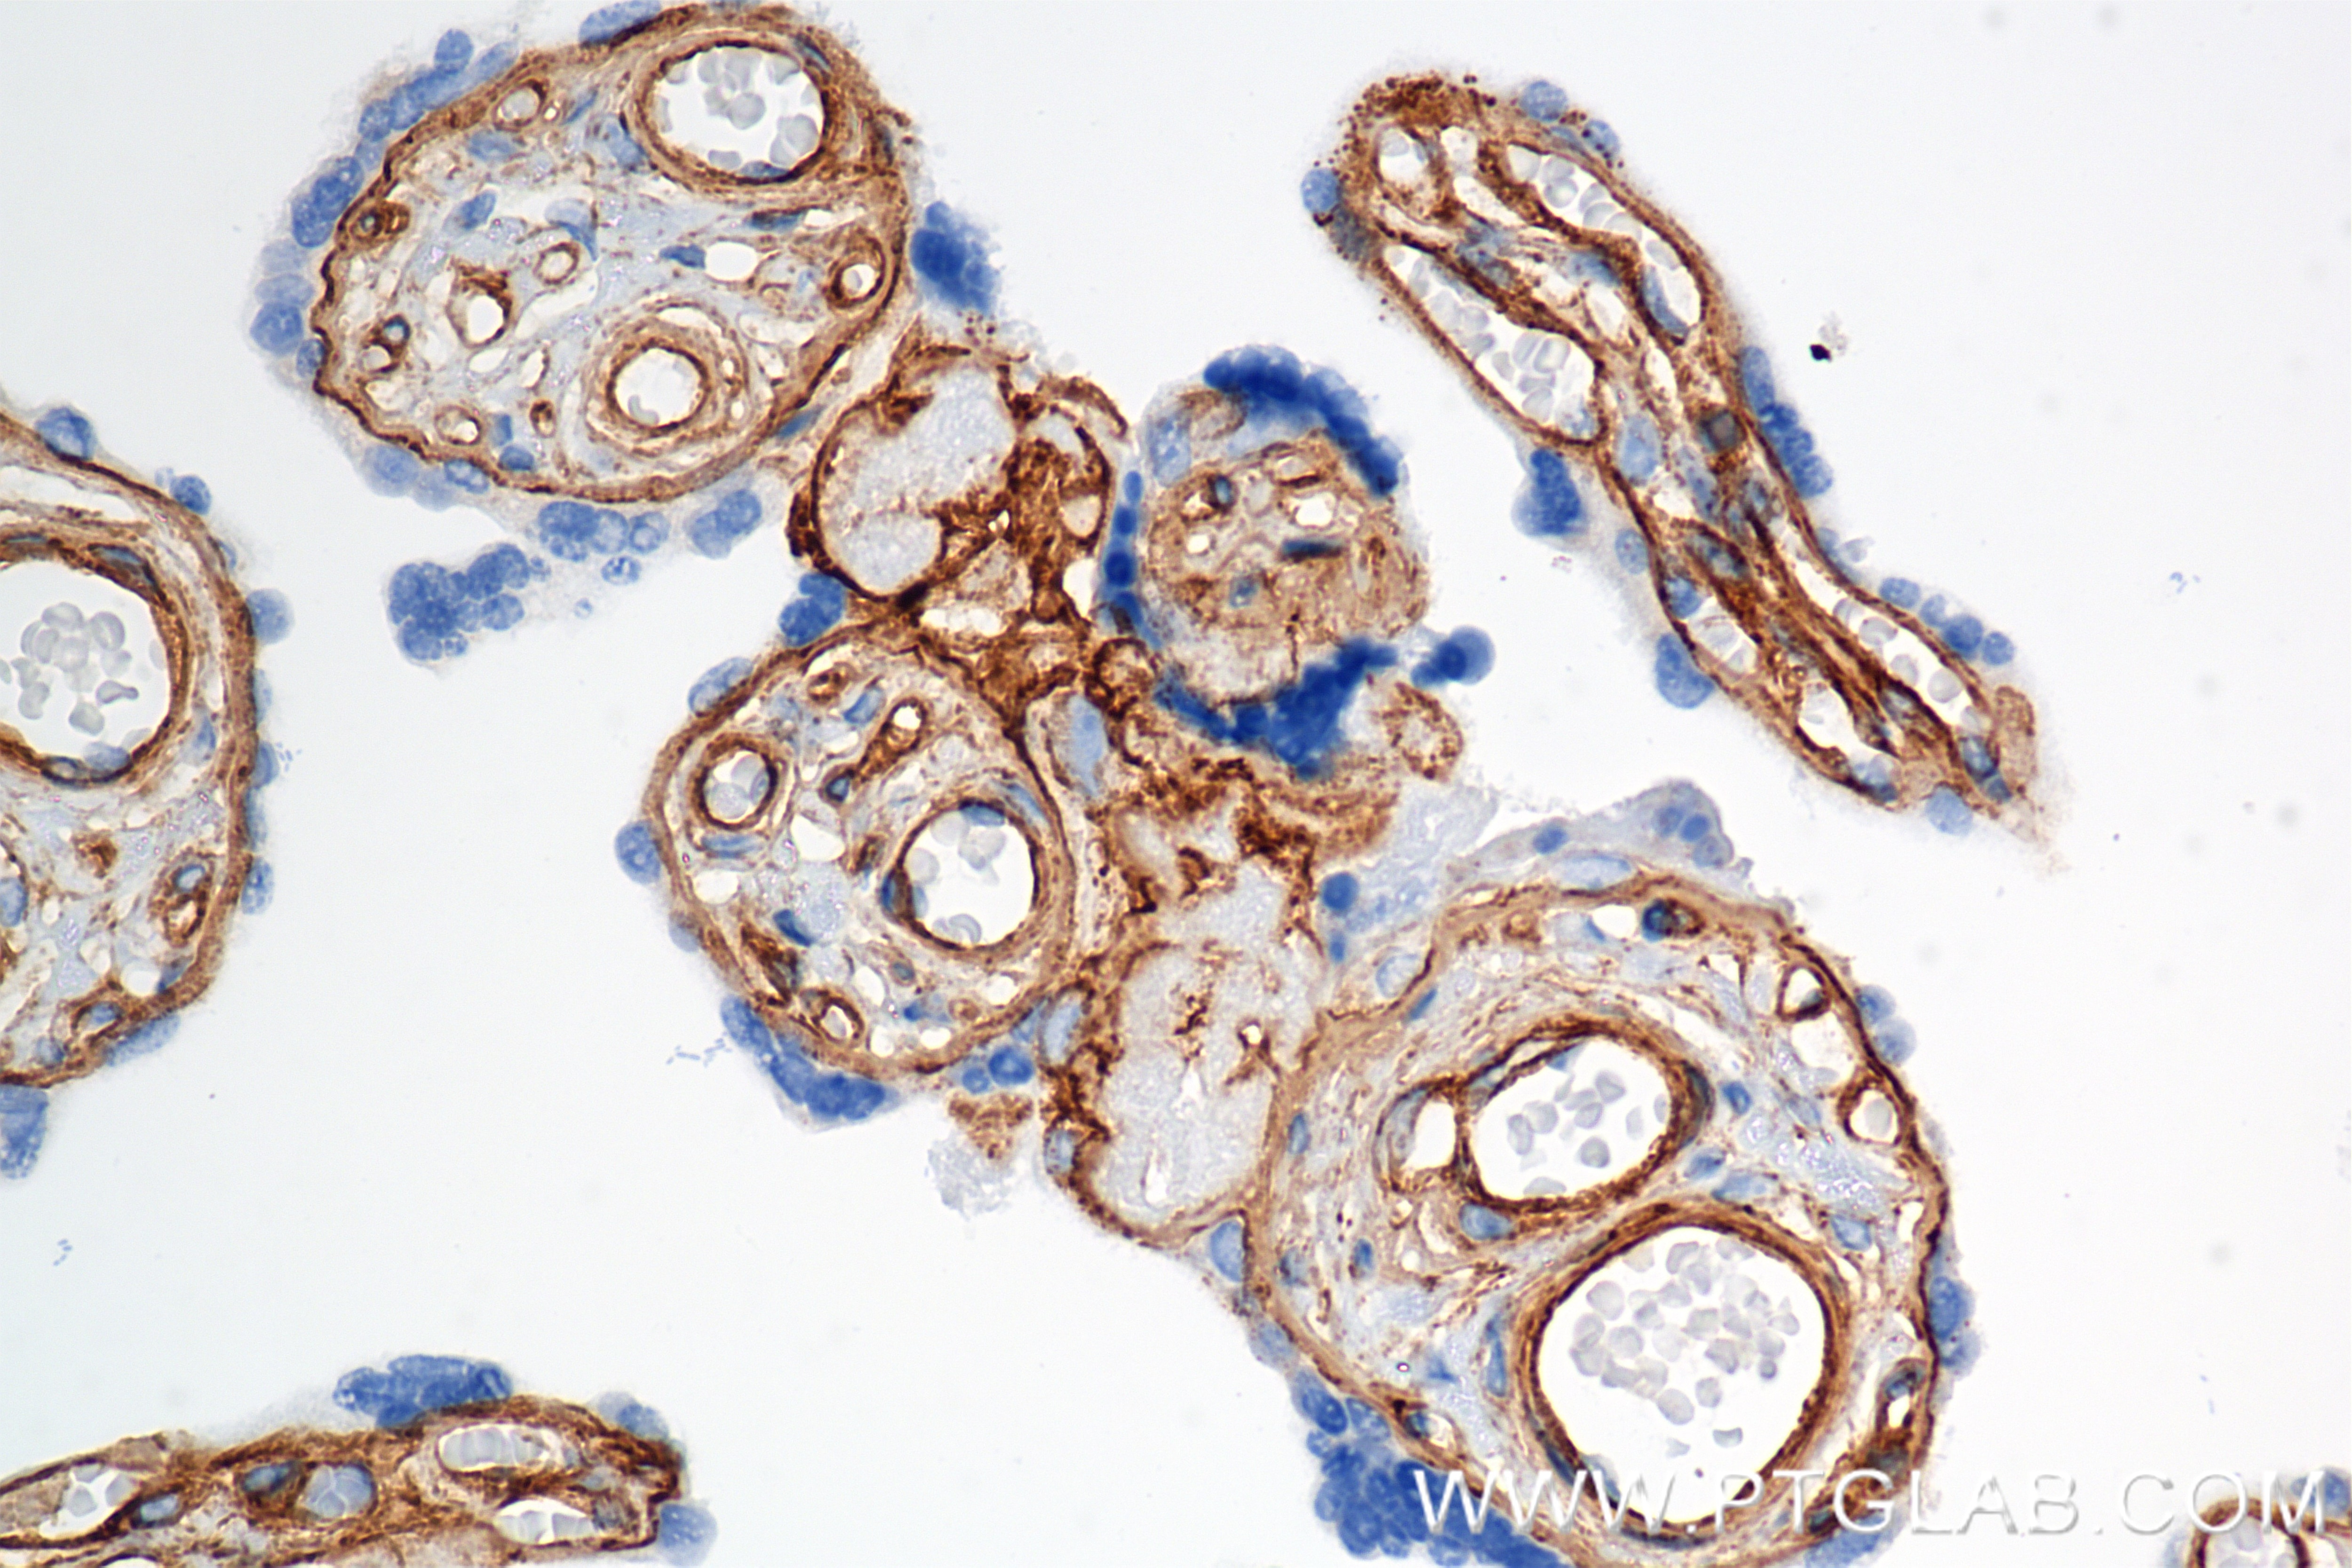

85256-4-PBS targets COL4A1 in WB, IHC, Indirect ELISA applications and shows reactivity with human samples.

COL4A1 (Collagen Type IV Alpha 1 Chain) encodes a major component of type IV collagen, which is an essential structural element of basement membranes in various tissues. COL4A1 forms heterotrimers with other collagen type IV chains (e.g., COL4A2) and interacts with extracellular matrix components such as laminins, proteoglycans, and perlecans. Proteolytic cleavage of the non-collagenous domain of COL4A1 produces a fragment called arresten, which has anti-angiogenic and tumor suppressor properties. Elevated expression of COL4A1 has been observed in various cancers, including hepatocellular carcinoma (HCC), where it promotes tumor growth and metastasis through the FAK-Src signaling pathway. COL4A1 is highly expressed in various tissues, including the placenta, fat, and other organs. The expression of COL4A1 can be regulated by transcription factors such as RUNX1, which has been shown to upregulate COL4A1 in hepatocellular carcinoma.